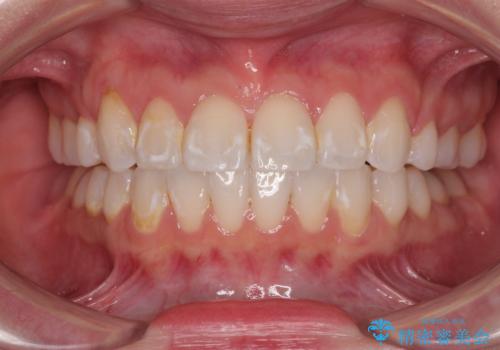

八重歯と下の歯のがたつき マウスピースで

担当医 井上季実子